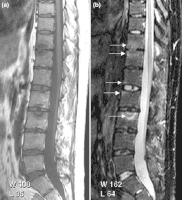

(a) T1-weighted and (b) short tau inversion recovery (STIR) magnetic resonance images of lumbar and lower thoracic spine in psoriatic arthritis. Signs of active inflammation are seen at several levels (arrows). In particular, anterior spondylitis is seen at level L1/L2 and an inflammatory Andersson lesion at the upper vertebral endplate of L3. -